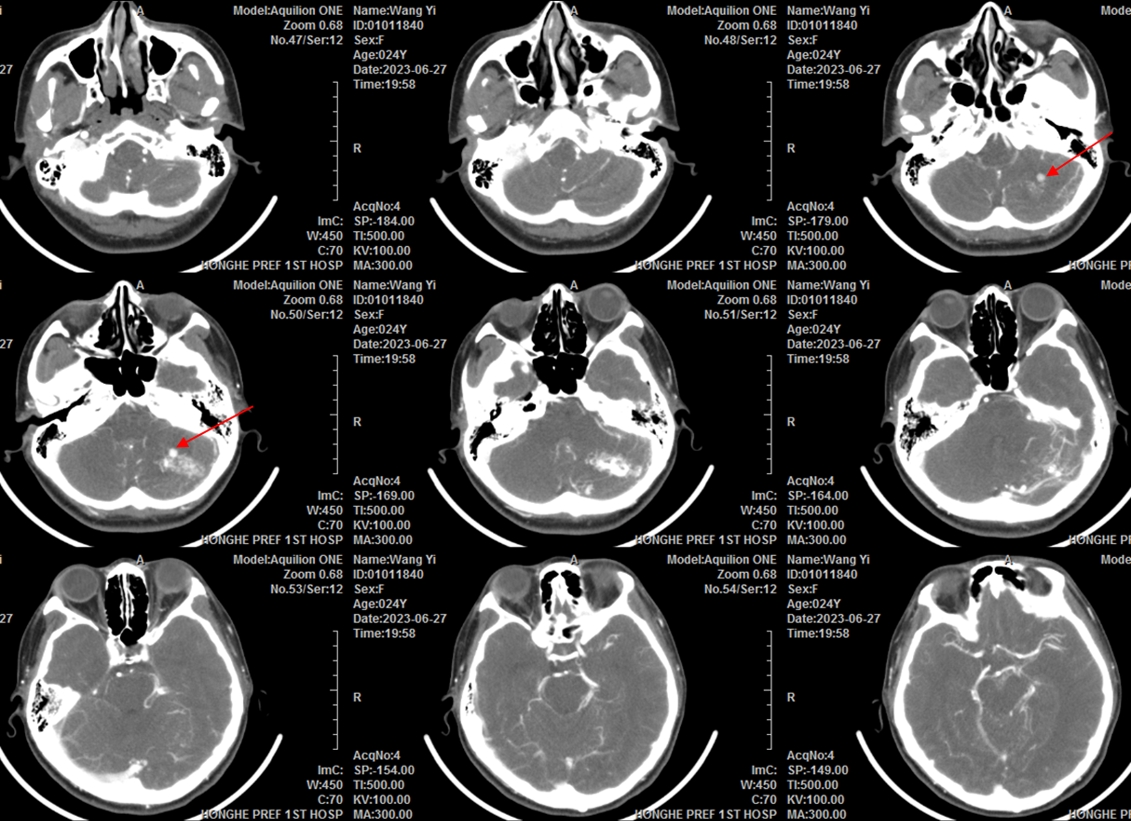

急诊CT提示左侧小脑半球出血。

已有左侧脑干受压表现(黄色箭头)

急诊CTA提示左侧小脑半球动静脉畸形,畸形血管团深面可见血流相关性动脉瘤或扩张的静脉球(红色箭头)